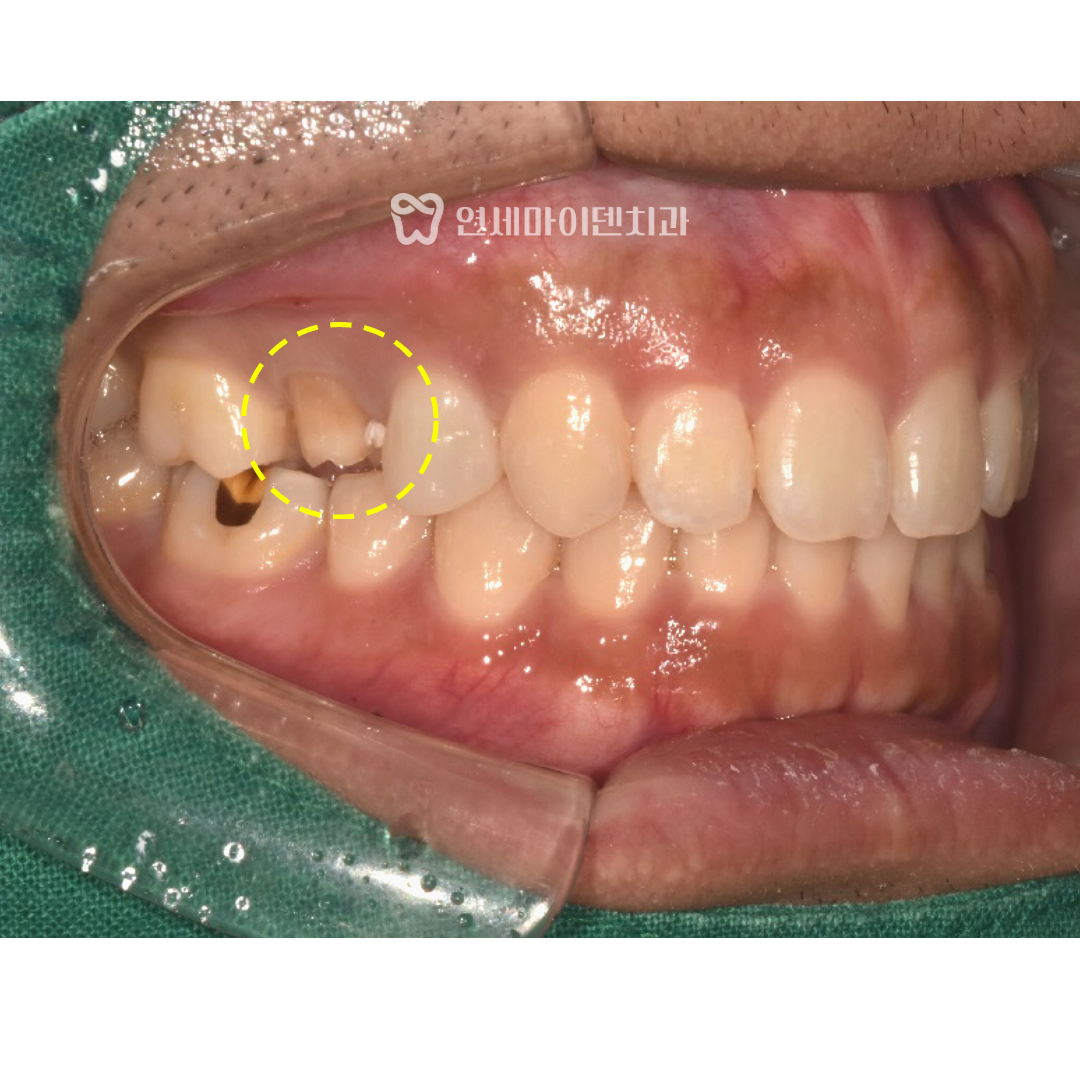

기존 크라운을 제거해보니

치아 옆쪽에 충치가 상당히 진행되어 있었습니다.

겉으로 보기에는 멀쩡했지만, 내부에서 서서히 진행되어

옆 치아까지 영향을 줄 수 있는 상황이었습니다.